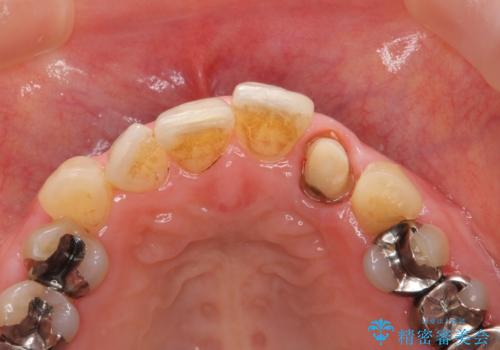

- 目立つ前歯の著しい変色の改善を求めて来院されました。

根管治療が為されたまま、クラウンの装着が行われず変色し審美障害を来している状態です。

維持を保つためのファイバーコア築盛を行い、精密なジルコニアクラウン製作を行います。